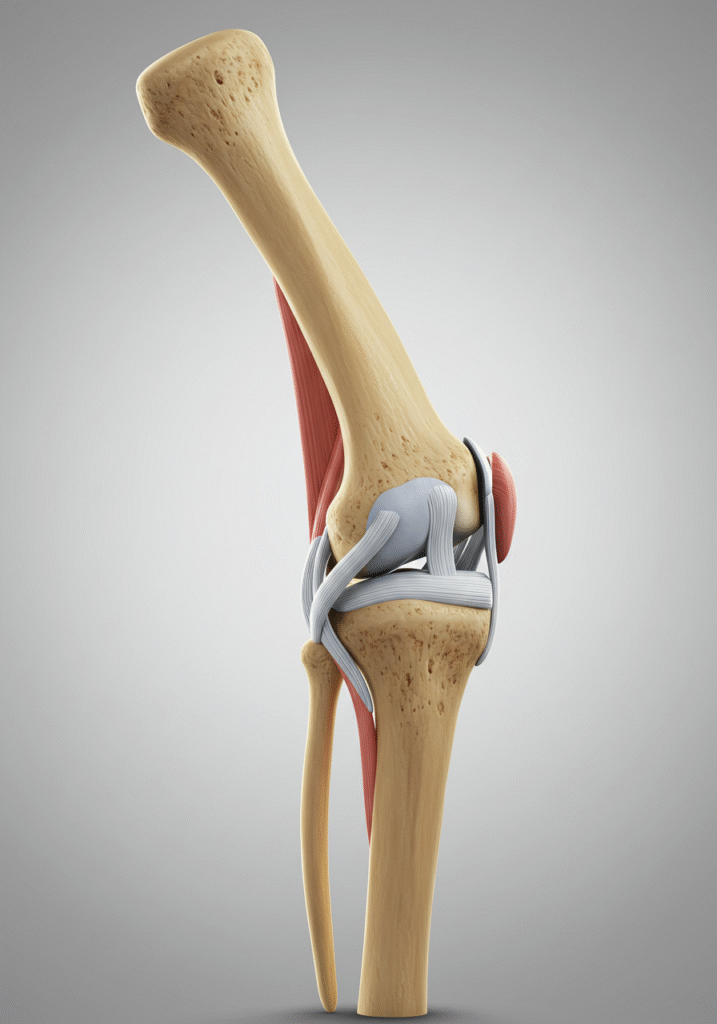

Lesión de Ligamentos de la Rodilla

¿Qué es?

Ruptura o distensión de los ligamentos cruzados o colaterales, esenciales para la estabilidad.

Lesión de Meniscos

¿Qué es?

Es la rotura del cartílago en forma de “C” que amortigua la articulación.